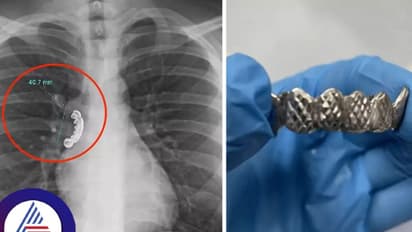

ನಂಬೋಕೆ ಕಷ್ಟವಾದರೂ ಇದು ನಿಜ. 22 ವರ್ಷದ ವ್ಯಕ್ತಿ, ಆಕಸ್ಮಿಕವಾಗಿ ದಂತಗಳನ್ನು ನುಂಗಿದ್ದು, ನಂತರ ಇದು ಶ್ವಾಸಕೋಶದಲ್ಲಿ ಸಿಲುಕಿ ಹಾಕಿಕೊಂಡಿದೆ. ವಿಸ್ಕಾನ್ಸಿನ್ನ ವ್ಯಕ್ತಿಯೊಬ್ಬ ಬೆಳ್ಳಿಯ ನಕಲಿ ಹಲ್ಲಿನ ಸೆಟ್ನ್ನು ದರಿಸಿದ್ದಾನೆ. ಆದರೆ ಆಹಾರ ಸೇವಿಸುವಾಗ ಆಕಸ್ಮಿಕವಾಗಿ ಹಲ್ಲಿನ ಸೆಟ್ನ್ನು ನುಂಗಿಬಿಟ್ಟಿದ್ದಾನೆ. ಇದರ ಪರಿಣಾಮವಾಗಿ ವ್ಯಕ್ತಿಯಲ್ಲಿ ಭಾರೀ ಕೆಮ್ಮು ಮತ್ತು ಉಬ್ಬಸ ಕಾಣಿಸಿಕೊಂಡಿತು.

ಶ್ವಾಸನಾಳದಲ್ಲಿತ್ತು 1.5 ಇಂಚಿನ ಹಲ್ಲಿನ ಸೆಟ್

ಕ್ಯುರಸ್ ವೈದ್ಯಕೀಯ ಜರ್ನಲ್ನಲ್ಲಿ ಈ ವಾರ ಪ್ರಕಟವಾದ ಕೇಸ್ ಸ್ಟಡಿ ಪ್ರಕಾರ, ವ್ಯಕ್ತಿಯನ್ನು ಆಸ್ಪತ್ರೆಗೆ (Hospital) ಕರೆದೊಯ್ದು ಎಕ್ಸ್ರೇ ತೆಗೆಯಲಾಯಿತು. ಈ ಸಂದರ್ಭದಲ್ಲಿ ಅವರ ಶ್ವಾಸನಾಳದಲ್ಲಿ (Lungs) 1.5 ಇಂಚಿನ ಹಲ್ಲಿನ ಸೆಟ್ ಸಿಲುಕಿಕೊಂಡಿರೋದು ತಿಳಿದುಬಂತು. ನಂತರ ವೈದ್ಯರು ಬ್ರೋನೋಸ್ಕೋಪಿ ಮಾಡಿ ಶ್ವಾಸನಾಳದಲ್ಲಿ ಸಿಲುಕಿದ್ದ ಹಲ್ಲಿನ ಸೆಟ್ನ್ನು ಹೊರತೆಗೆದರು. ಬ್ರೋನೋಸ್ಕೋಪಿ ಎಂಬುದು ಶ್ವಾಸಕೋಶಕ್ಕೆ ಫ್ಲೆಕ್ಸಿಬಲ್ ಟ್ಯೂಬ್, ಬ್ರೋನೋಸ್ಕೋಪ್ನ್ನು ಬಳಸಿ ಸಿಲುಕಿಹಾಕಿಕೊಂಡಿರುವ ವಸ್ತುವನ್ನು ಹೊರತೆಗೆಯುವ ವಿಧಾನವಾಗಿದೆ.